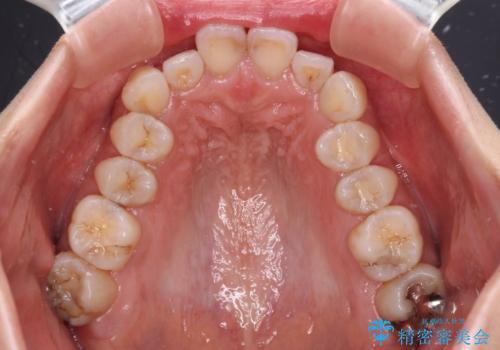

- デコボコと飛び出している前歯を気にして来院された患者様です。

歯列としてはインビザラインでもワイヤー矯正でも対応できるものでしたが、奥歯の咬み合わせを見た時に上顎がやや前方にあり、インビザライン単独では時間のかかってしまう可能性があるため、補助装置を治療当初に使用することで、インビザラインによる治療をスムーズに行えるように計画しました。